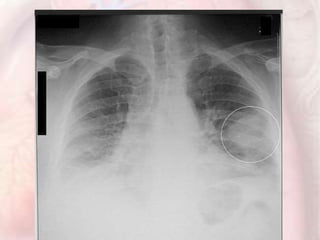

Chest X-Ray

Study of 2,322 patients with PE:

 Cardiac enlargement (27%)

 Normal (24%)

 Pleural effusion (23%)

 Elevated hemidiaphragm (20%)

 Pulmonary artery enlargement (19%)

 Atelectasis (18%)

 Parenchymal pulmonary infiltrates (17%)

•Usually abnormal, but non-specific most

useful for excluding other conditions.

Chest Radiographs in Acute Pulmonary Embolism: Results From the International Cooperative Pulmonary Embolism Registry. Chest July

2000 118:3338; 10.1378/chest.118.1.33

Westermark sign ?

Hampton hump ?

Hampton hump : a peripheral conical density with

the base apposed to the chest wall

more specific but are not commonly seen

The Westermark sign : focal oligemia distal

to a PE